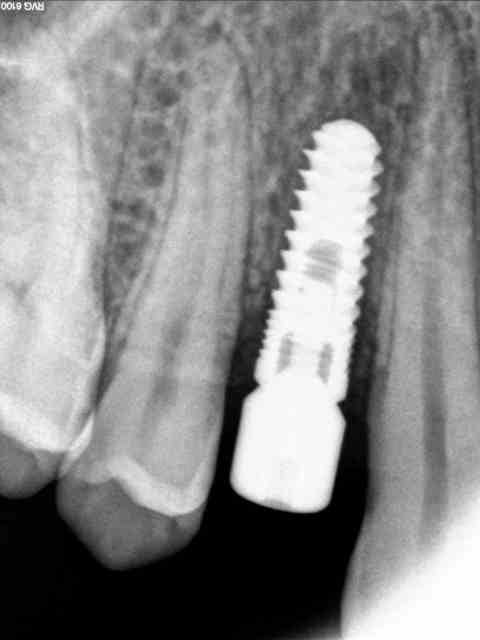

Je post le cliché de ce matin.

la radio

à la radio, j'aime pas les zones sombres en regard de tes spires...

Pour l'image radio, c'est les filtres du logiciel trophy qui donne systématiquement cette impression (ça le fait sur tous mes implants ;)